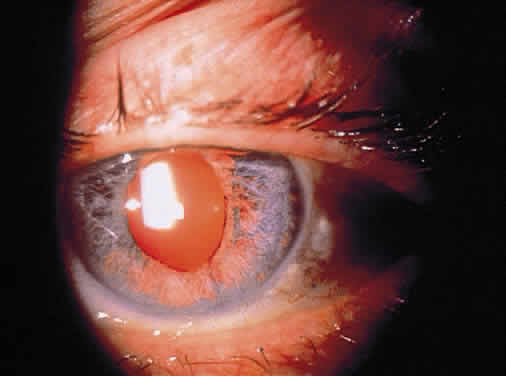

In addition to size, shape, and distribution of keratic precipitates, color may be an important characteristic. Fresh keratic precipitates tend to be white and round, whereas older keratic precipitates may be pigmented, faded, or have an irregular crenelated appearance. Descemet's membrane may cover old keratic precipitates, imparting a glassy or ghost-like appearance (Fig. 3). Large greasy-white keratic precipitates approaching 1 mm in diameter are often termed mutton-fat keratic precipitates and represent clusters of macrophages and epithelioid cells (Fig. 4). These are pathognomonic of granulomatous inflammation.

Although many keratic precipitates fade without sequelae, transient decompensation of the cornea may ensue. The endothelium may have the appearance of having guttae (cornea pseudoguttata) secondary to endothelial cell swelling.9 Permanent opacification of the inferior corneal endothelium has also been described in chronic iridocyclitis, resulting from fibrous metaplasia of the endothelium due to the presence of keratic precipitates10 (see Fig. 3). It is important to document size, color, distribution, and number of keratic precipitates at each visit. For example, one should describe 30 small white keratic precipitates and 5 medium pigmented keratic precipitates all located on the inferior cornea, rather than simply noting that the patient has keratic precipitates.

Posterior synechiae may also develop without nodule formation because fibrin in the aqueous can induce adhesions to the lens. Later, fibrous organization may make adhesions pharmacologically unbreakable, and the formation of synechiae during treatment indicates inadequate therapy. If posterior synechia formation proceeds unchecked, pupillary block glaucoma may develop (Fig. 8). Peripheral anterior synechiae (PAS) in the anterior chamber angle may result from chronic shallowing of the anterior chamber because of posterior synechiae and pupillary block. They may also result from fibrous organization of inflammatory exudates and precipitates in the angle. Rubeosis may also occur in severe long-standing uveitis and lead to PAS. Progression of PAS may lead to angleclosure glaucoma.